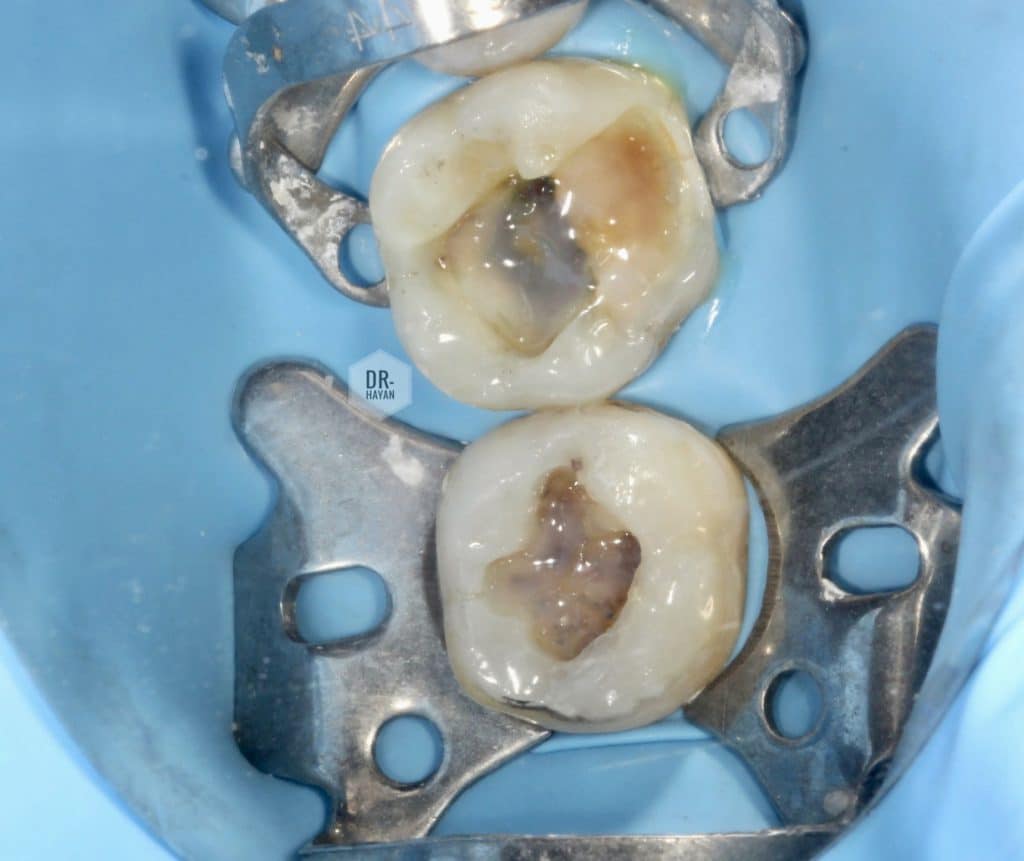

After complete soft caries removal

Amalgam tattoo & hard discoloration dentine on floor of cavity

- After etching dis infected the cavity by CHX

And dry it only

CHX is recommended to be used in case

Etching, drillind , heat generation in dentine

as those causes degeneration of collagen protein from hydroxyapatite which makes it vulnerable to the action of proteolytic enzymes such as MMPs … is there a recommendation to use CHX to prevent it degeneration

Bonding process

Used dentsply sirona universal bond

Bonding

, universal bond

2 layer

Bond 👉🏻 rubbing 20 s remove excess 👉🏻 some air 👉🏻 light cure 20 s

Another one

One layer of universal bond it’s very weak And thickness of one layer about 10 micron

When application 2 layer - we elevated the thickness of adhesive layer to 20 micron

Still it’s weak point in universal bond

O.5 mm of RESIN COATING on dentin

Used dentsply neo st flow

Buccal wall bulding up

Compsite use : dentsply neo spectra ST/ LV